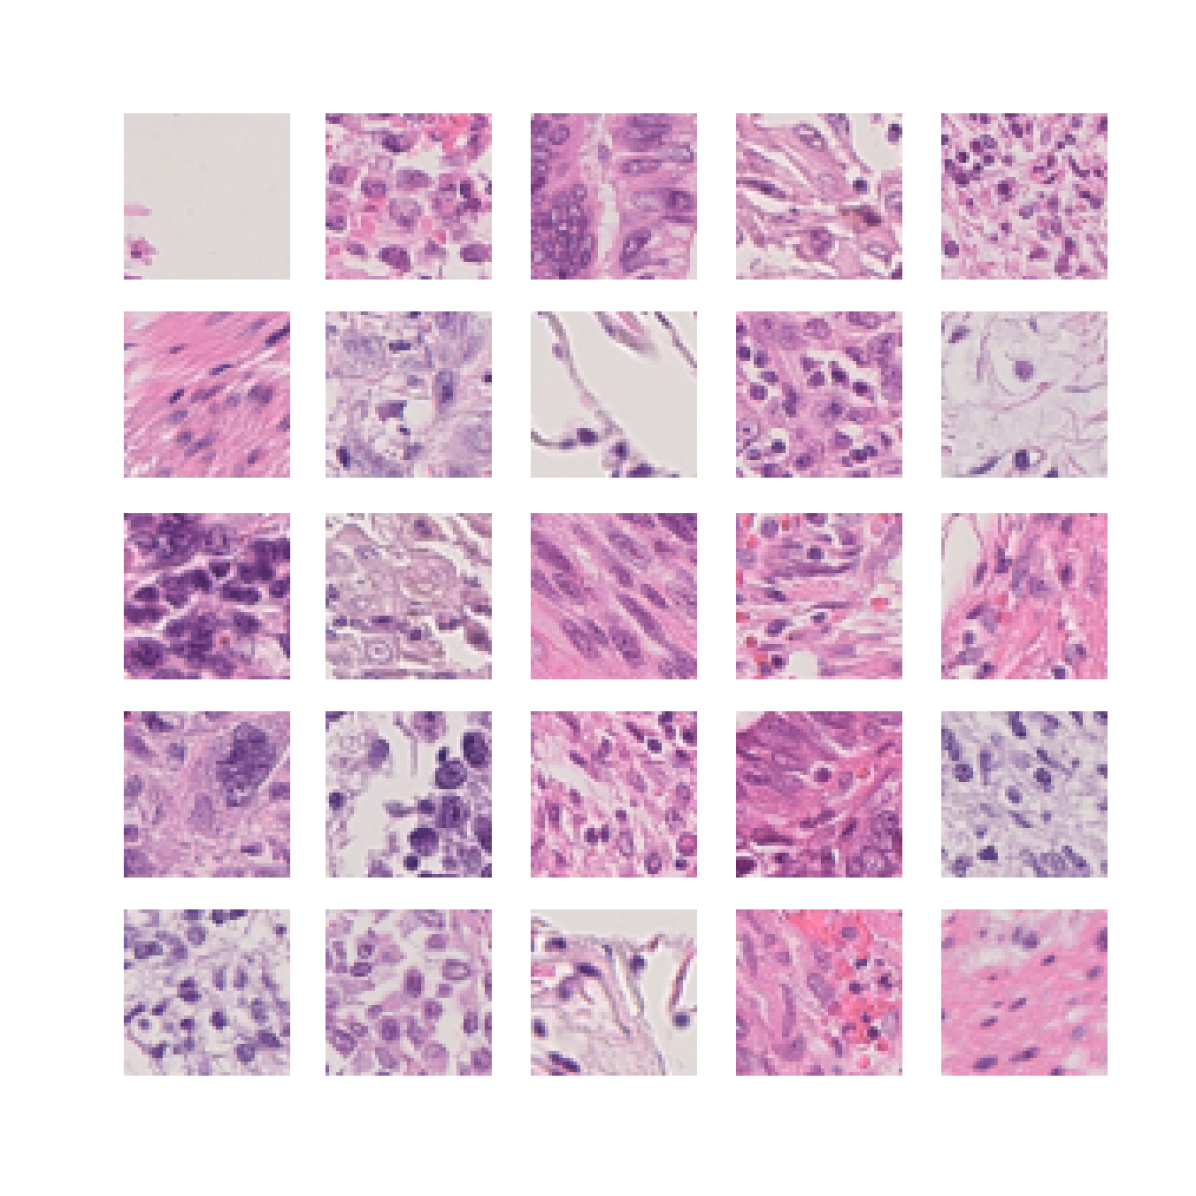

We first demonstrate that TriDeNT ♆ is highly effective for improving the quality of representations in the primary encoder by distilling privileged information from immunofluorescence (IF) images to H&E stained images (Figure 2 and Table S6). Models are trained on the SegPath dataset [22], which consists of eight subsets of H&E images paired with an image derived from the IF stain of a consecutive slice for one of eight antibodies. Evaluation is performed on four standard computational pathology tasks (see Section S2 for full details). We find that the model significantly increases performance by up to 101% compared to a privileged baseline model. TriDeNT ♆ retains not only the useful features shared between inputs, but also the features which are only present in the primary data, leading to better performance on all evaluated tasks. Even in cases where the privileged data does not appear to significantly improve performance, such as staining with CD235a, TriDeNT ♆ still achieves comparable performance, as it obtains a strong supervisory signal from the additional H&E branch. This is in contrast with the privileged Siamese setting, where it is clear that the pairing can cause a seismic drop in classification accuracy if the privileged data is not informative for the task being evaluated.

To further analyse the learned representations, we produce UMAP projections of the latent space labelled with the tissue types for the NCT tissue type classification task, as shown for CD3CD20 and SMA in Figure 4(a), and for all SegPath stains in Figures S8 and S9. These figures make the reasons for the varying performance of the privileged Siamese model more apparent. For stains with better performing privileged Siamese models, such as SMA, the UMAPs are very similar between Siamese methods and TriDeNT, with well-differentiated tissue type clusters. In those with worse performance, such as ERG, the tissue types are poorly differentiated, often with only adipose and background forming distinct clusters from the other classes. On closer inspection, it is notable in these projections that TriDeNT ♆ produces more well-defined and separated clusters in general than Siamese networks. This is further evidenced in Figure S7, where TriDeNT ♆ is shown to identify clusters with overexpression of a given gene significantly more effectively than an unprivileged Siamese model.

We also analyse the activation maps for each model using GradCAM as described in section S3. This offers more insight into the areas of the image which are contributing most heavily to the models’ representations. In Figure 4(b) we present some representative examples, however, a larger selection which was chosen at random is presented in Figures S10 to S25. The larger selection makes it easier to see the emergent patterns, including that privileged Siamese models tend to mainly identify features which are strongly present in both inputs, while unprivileged Siamese models tend to learn more diffuse features that are not specific to one cell phenotype or image region. TriDeNT ♆ incorporates both sets of features, learning both features specific to the privileged data and more the general features associated with unprivileged Siamese networks.